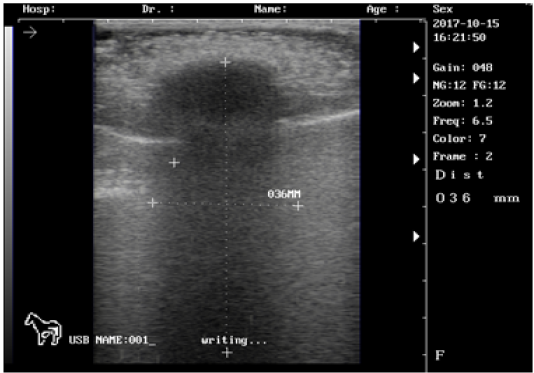

Ultrasound images of the testis of 3 months lamb showing: moderate echogenicity of the testicular parenchyma; mediastinum testicular highly echogenic